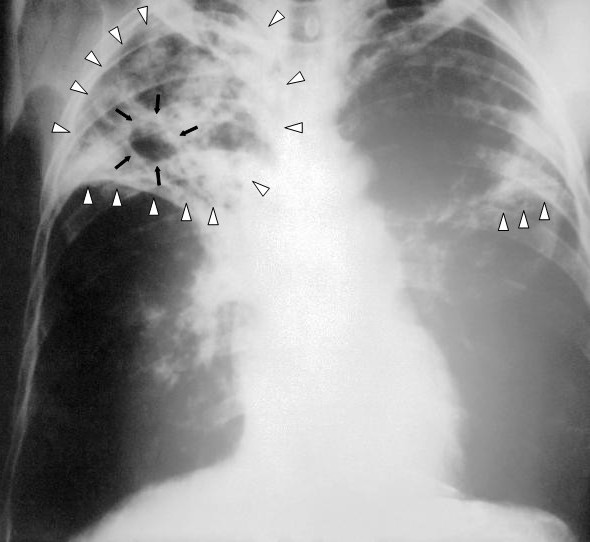

結核(けっかく、Tuberculosis 略:TB)とは、マイコバクテリウム属の細菌、主に結核菌(Mycobacterium tuberculosis)により引き起こされる感染症。結核菌は1882年に医師・細菌学者であったロベルト・コッホによって発見された。 好発部位は肺であるが、全身の臓器・器官に感染し、顕著な症状を呈している部位名の前後に「結核」を付け加えるなどした呼び方により細分化される(肺結核、肺外結核、カリエス参照)。 世界人口の約4分の1が結核菌に感染しており、その中の5‐10%が結核を発症する。抗菌剤が効かない多剤耐性肺結核(MDR-TB)や「超多剤耐性」(XDR)の薬剤耐性が問題となっている。 感染経路は結核菌を含む飛沫核の吸入による空気感染で、結核を発症した患者の咳、くしゃみ、唾液が原因となる一方、非発症者は排出源とならない。 結核の名は、炎症を起こす結核菌の周囲を炎症し